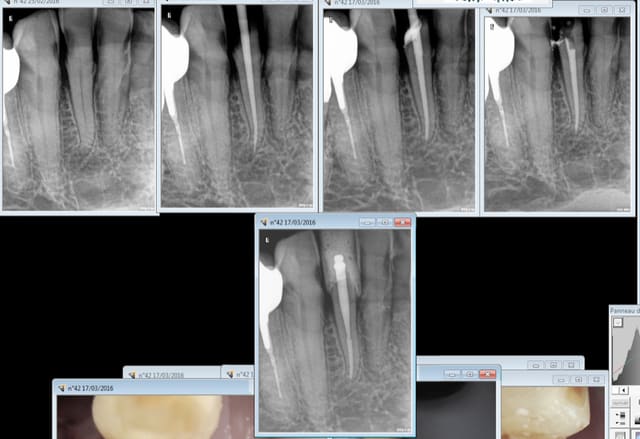

42, endo taille empreinte provisoire 1H.

Je "fidélise" la 43. Trop chiante à soigner pour un tarif de merde. -)

Capture d e cran 2016 03 17 11.17 - Eugenol

Capture d e cran 2016 03 17 11.15 - Eugenol